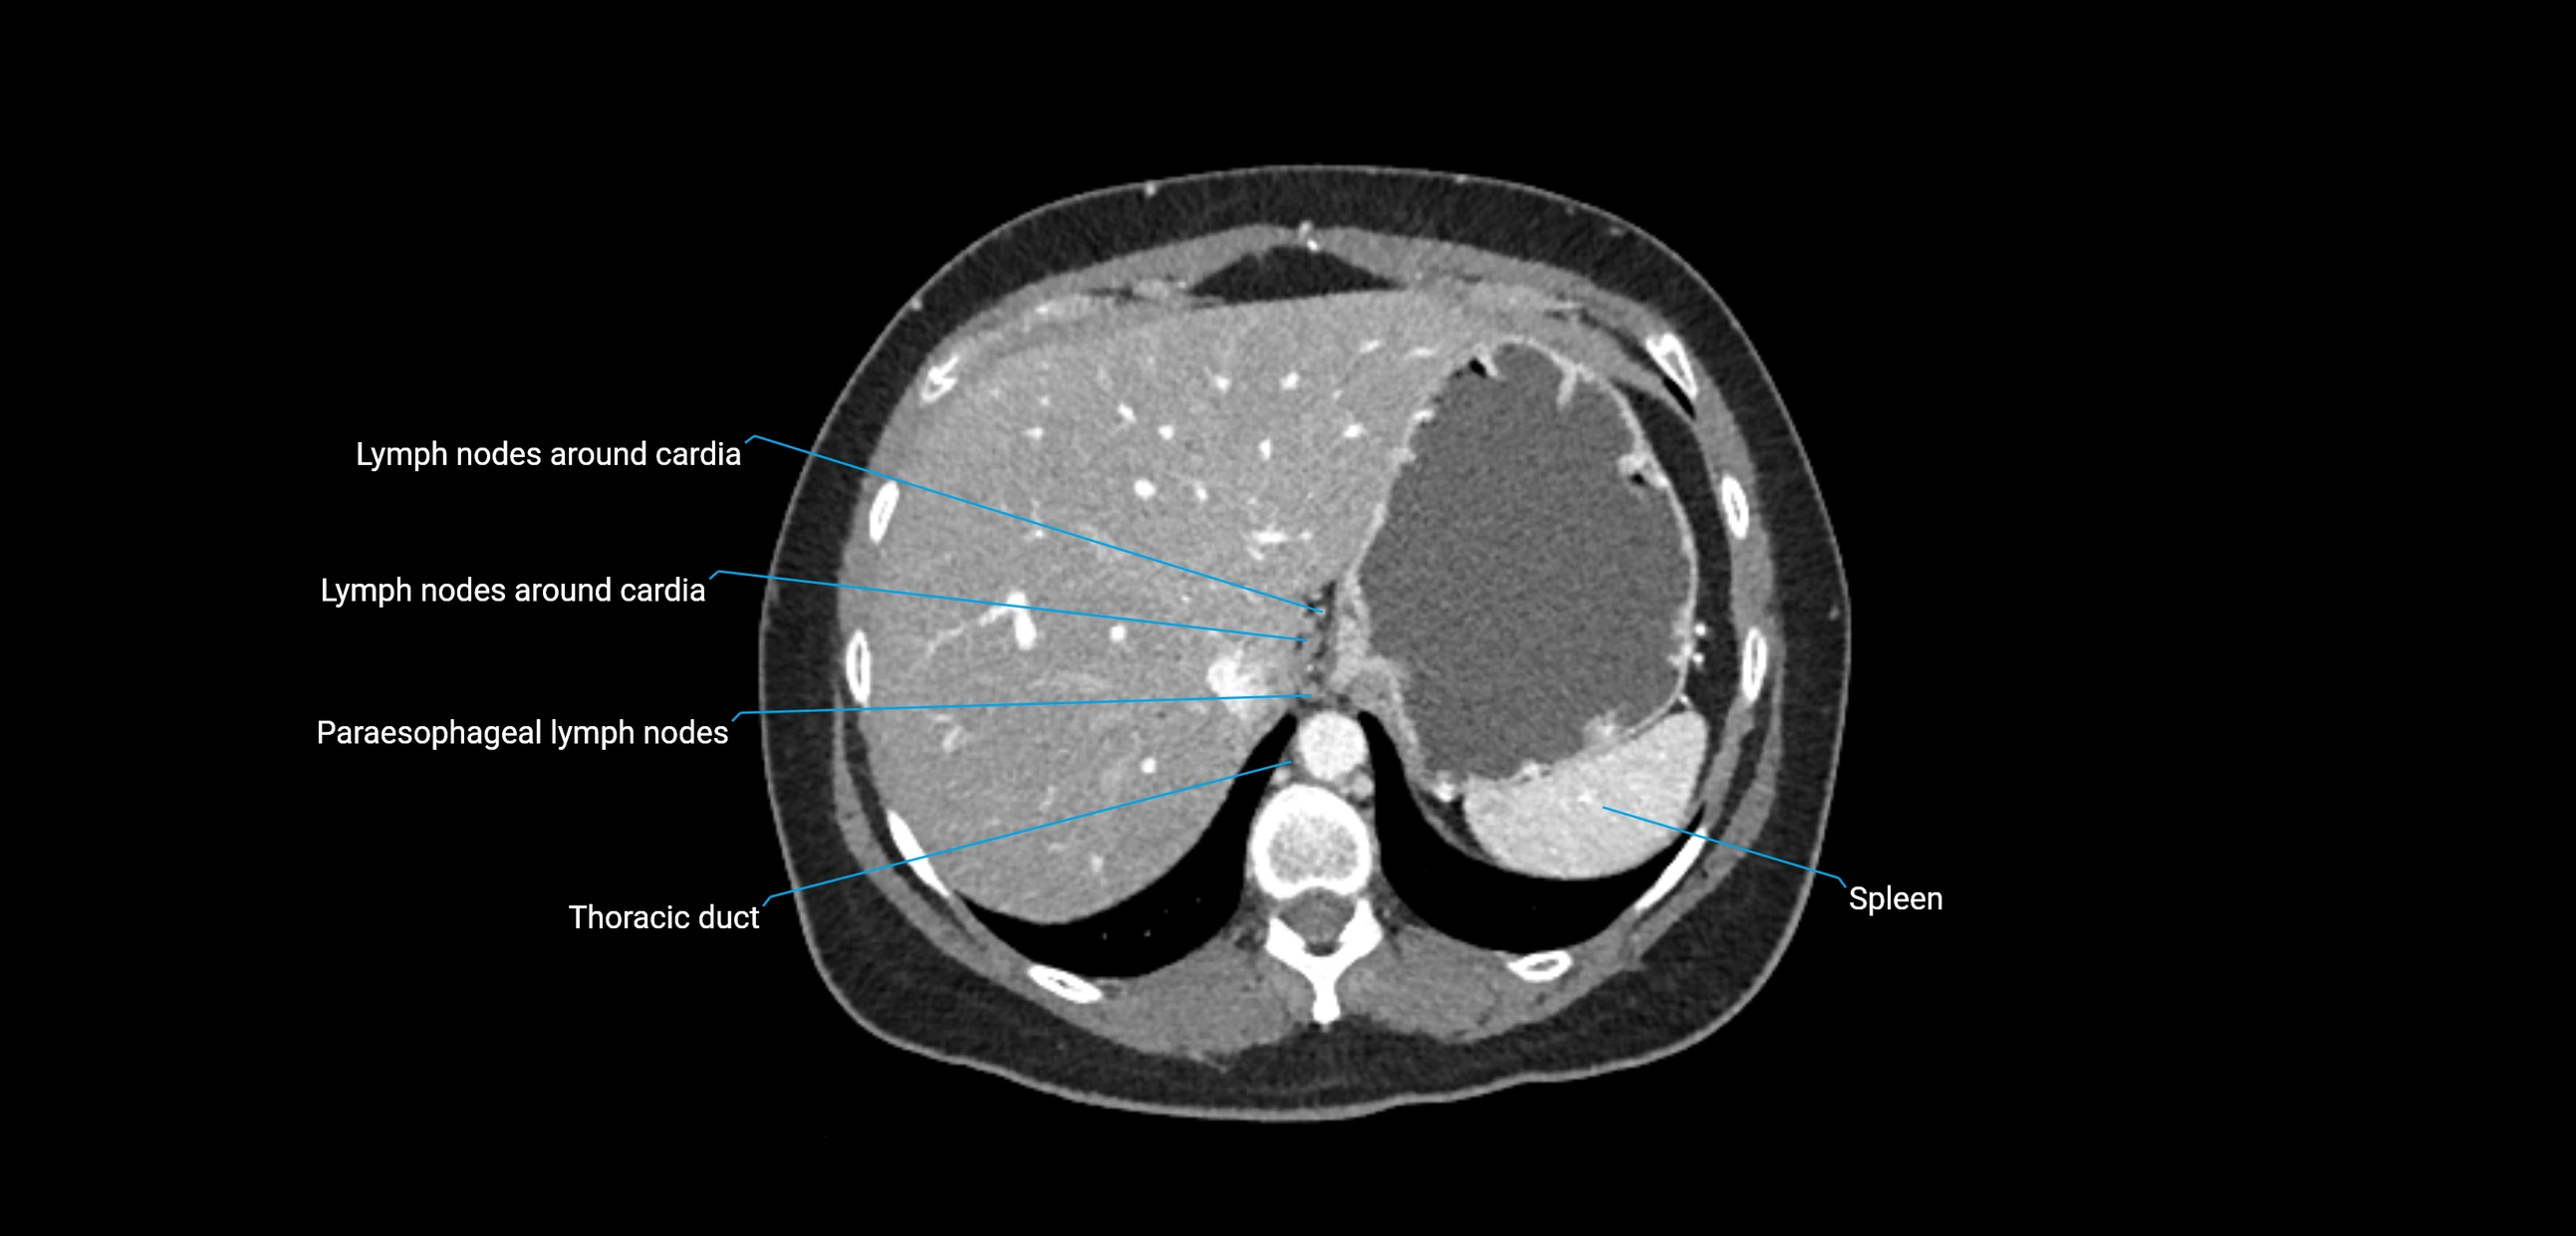

CT image

image